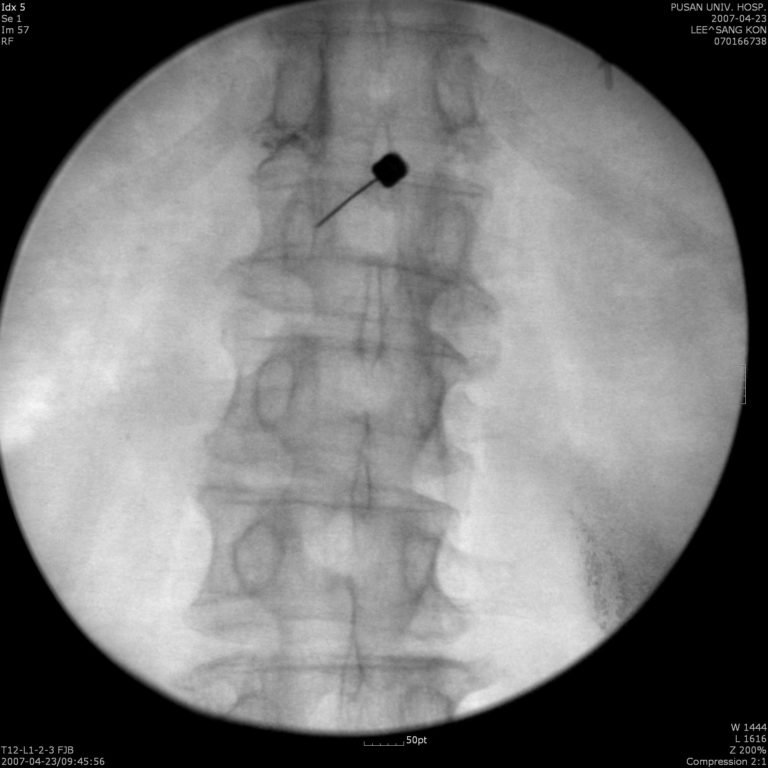

Διήθηση Μεσοσπονδυλίων αρθρώσεων (facet joint blocks)

Περιλαμβάνει την έγχυση στεροειδούς και τοπικού αναισθητικού μέσα στην εκφυλισμένη μεσοσπονδύλια άρθρωση (Σπονδυλαρθρίτιδα) για χρόνιο επίμονο πόνο.

Γίνεται με λίγη τοπική αναισθησία και είναι ανώδυνη τεχνική, με άριστα αποτελέσματα

Συνήθως διηθούνται περισσότερες από μία αρθρώσεις, συχνά 4 ή και παραπάνω αναλόγως των συμπτωμάτων.

Ο ασθενής νοσηλεύεται για 2 ώρες περίπου κι έπειτα πηγαίνει σπίτι του/της. Τα αποτελέσματα φαίνονται άμεσα, από την επόμενη

κιόλας ημέρα και μπορεί να κρατήσουν για μεγάλο διάστημα  (ανακούφιση ακόμη κι ένα έτος ή παραπάνω)